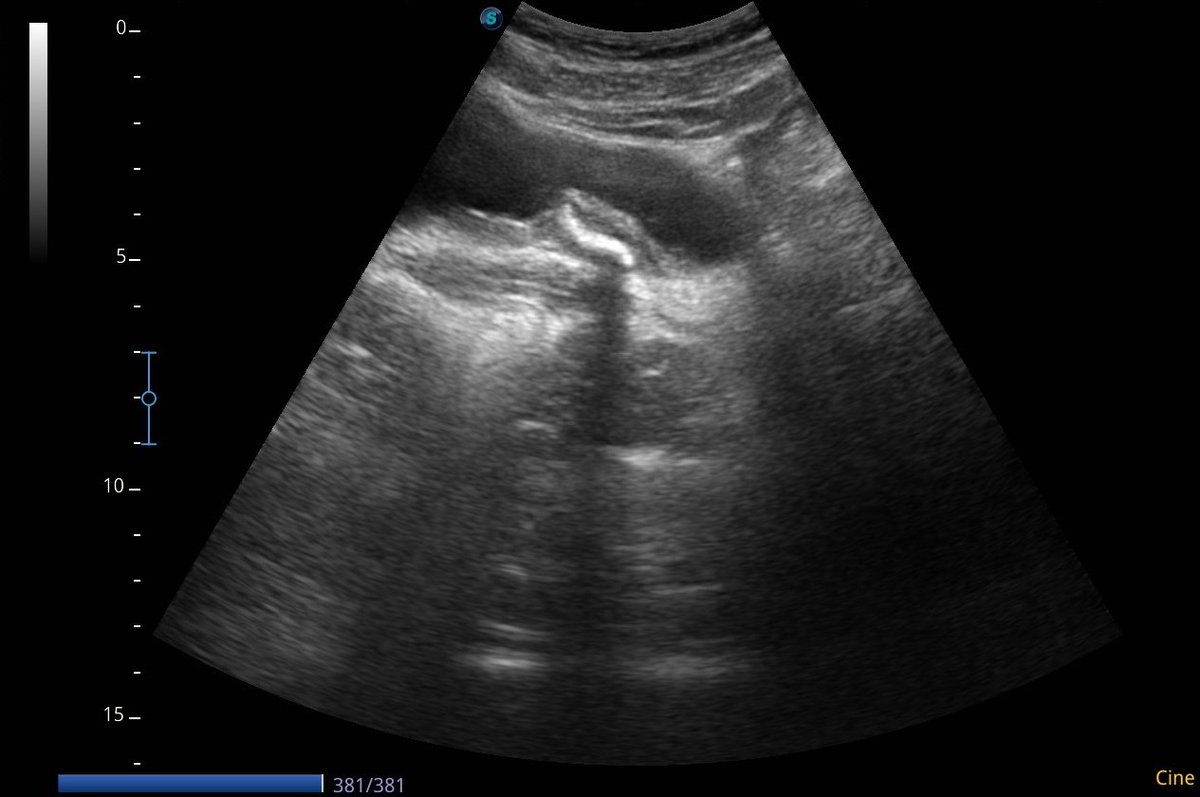

Complete fragmentation of a distal ureteral stone by #ESWL. Radiological and Ultrasound verification. Small stones are also fun!! @FPuigvert @oangerri @koey_kana @paoloverri05 @a_bravo_balado @joanfundi